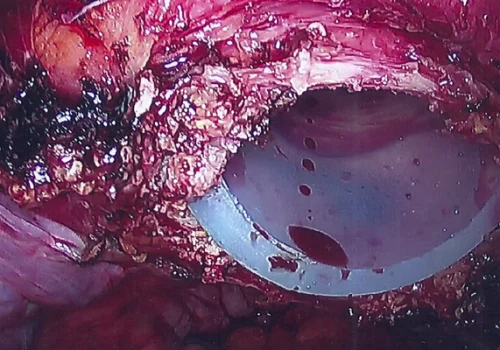

Procedure

She subsequently underwent Total Laparoscopic Hysterectomy and removal of both Tubes and Ovaries.